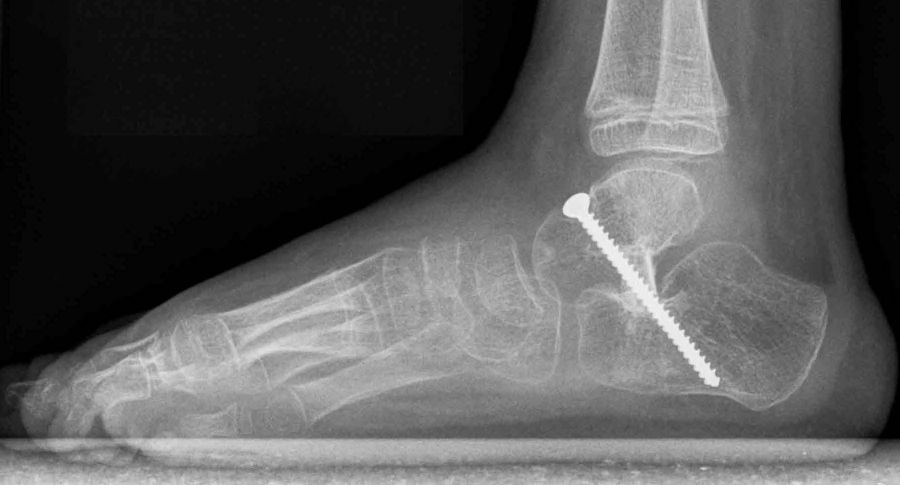

• Röntgenkontrolle (Bild 21,22).

• Im dargestellten Fall war zusätzlich eine plantarflektierende Cuneiforme mediale Osteotomie mit resorbierbarem Knochenersatz und eine Wadenmuskeldissektion nach Vulpius durchgeführt worden.

• Röntgen des dargestellten Falles 3 Monate post OP (Bild 25,26)